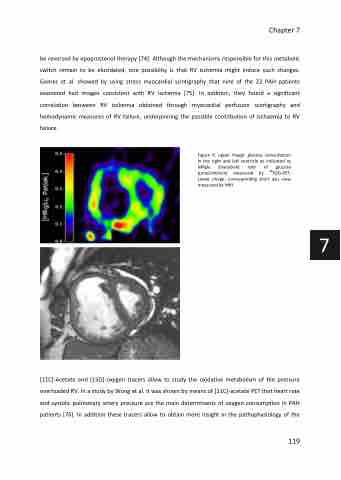

be reversed by epoprostenol therapy [74]. Although the mechanisms responsible for this metabolic switch remain to be elucidated, one possibility is that RV ischemia might induce such changes. Gomez et al. showed by using stress myocardial scintigraphy that nine of the 23 PAH patients examined had images consistent with RV ischemia [75]. In addition, they found a significant correlation between RV ischemia obtained through myocardial perfusion scintigraphy and hemodynamic measures of RV failure, underpinning the possible contribution of ischaemia to RV failure.

Figure 6: upper image: glucose consumption in the right and left ventricle as indicated as

MRglu (metabolic rate

(μmol/ml/min) measured by

Lower image: corresponding short axis view measured by MRI

of glucose 18FDG-PET.